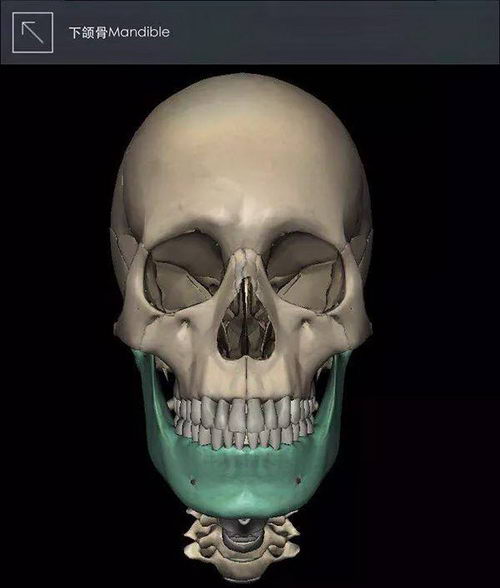

双鄂=上颚(上颌骨)+下颚(下颌骨)

(图中带颜色部位)

▲图片来自《3Dbody》

这里的骨骼凸出范围超过了牙槽骨,已经是上下颌骨凸出,我们称之为双鄂凸嘴手术。

并且可能伴随着咬合不正(位置不对)的情况,此时需要采取的是复杂的双鄂手术,上颚(上颌骨)和下颚(下颌骨)同时截断,重新矫正到理想的位置上,从而使患者拥有正确的咬合状态和脸型。

▲双鄂手术方式示意图

除了能改善双鄂突出导致的凸嘴以外,撅下巴(地包天)、长脸、面部不对称、咬合不正等也是在治疗的范围之内的。

▲双鄂手术可以改善咬合不正

手术的目的不仅仅是将凸出的嘴向后推几毫米, 让脸变得自然,美丽,此外也是可以矫正牙齿咬合不正,让咀嚼、发音、吞咽功能恢复正常。